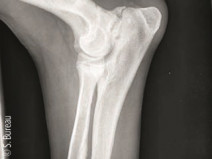

• Les boiteries du jeune

La section Sud-Est vous propose une journée de formation en pathologie orthopédique chez le jeune animal. A l'issue de cette formation, le participant devra être capable de réaliser un cliché radiographique de qualité et l'interpréter et de prendre en charge une affection du cartilage chez le jeune.